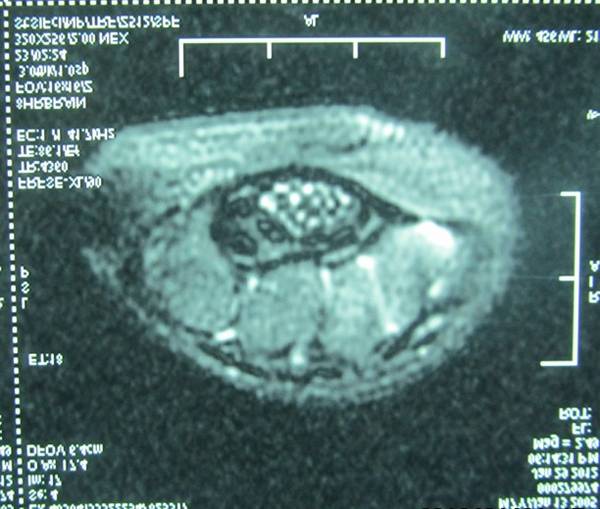

昨天手术一名神经纤维瘤病的患者。

术中电刺激定位鱼际肌的肌支后,就可以保留功能性神经束,大胆切除异常生长的脂肪、神经束膜及外膜。